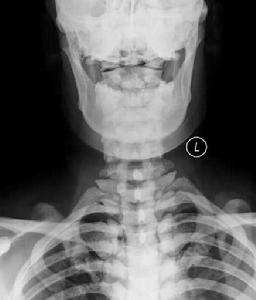

3.氟骨症的X線診斷分型與分度:X線照片要求骨紋顯示清晰,至少包括骨盆及側前壁、小腿正位。

(1)分型:按骨密度和結構的主要改變可分3型:①硬化型:主要有兩種:A.骨密度增高,骨小梁增粗,融合骨皮質增厚,髓腔變窄或消失。B.骨間膜及周圍韌帶骨化。②疏鬆型:亦可分為兩種情況:A.骨密度減低,骨小梁稀疏。骨質有不同程度的吸收脫鈣或造成骨骼變形。B.骨間膜或骨周韌帶骨化。③混合型:兼有以上兩者特點(同時存在不同程度的骨質增生及骨吸收)或松質骨呈網狀或囊狀結構,皮質骨結構鬆散單位面積內骨小梁數目明顯減少。

(2)分度:以上3型中都有不同程度的變化,可分為早期改變及輕、中、重3度。 ①早期改變:有下列徵象之一者可診斷為早期氟骨症:A.長骨骨端、骨盆骨僅見明顯成片的點狀紋理或有增粗紊亂的骨紋。B.四肢長骨皮質緣可出現兩處以上幼芽破土狀骨疣.橈骨脊處多呈波浪狀增生。②輕度:A.骨密度較正常略高,骨小梁粗密,出現骨斑,骨小梁變細,密度減低。B.肌肉韌帶附著處出現尖狀骨化,骨間膜明顯增生。③中度:A.骨密度明顯增高,皮質增厚,骨小梁增粗,部分融合;或有皮質變薄,骨小梁細而稀,密度降低,或骨小梁稀疏,但紋理粗大,密度增高。B.骨間膜及骨周韌帶有較大範圍之骨化。④重度:A.骨小梁增粗,大部分融合成片,髓腔皮質界限不清;或骨質疏鬆呈斑片狀吸收,皮質骨部分中斷消失骨變形較明顯。B.骨間膜及周圍韌帶骨化更明顯,可成橋形,並可出現其他軟組織(如血管)的鈣化影。

1.X線表現

(1)骨質疏鬆型:骨紋理粗而稀疏可為早期氟骨症的惟一表現。

(2)骨軟化症:以脊柱和骨盆明顯,其骨密度減低,紋理模糊。脊椎側彎、駝背。椎體雙凹變形骨盆縮窄畸形和假骨折線形成骨軟化可與骨質疏鬆,骨硬化和軟組織鈣化同時出現,呈混合型。

(3)骨硬化型:骨硬化常發生在脊柱、骨盆肋骨和顱骨。骨紋理粗如麻袋布或礫砂狀,嚴重者骨紋理融合,結構模糊,透X線度低而似象牙。骨硬化常伴四肢骨的骨端骨質疏鬆在顯著鈣攝入不足時可有繼發性甲旁亢此時四肢骨呈纖維囊性骨炎表現。